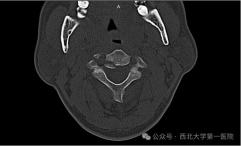

西北大学第一医院完成高难度创伤性枢椎滑脱骨折后路复位内固定术

近日,西北大学第一医院脊柱外科(骨科三病区)手术室内,一场紧张而关键的生命保卫战圆满落幕。医疗团队凭借精湛医术与紧密协...